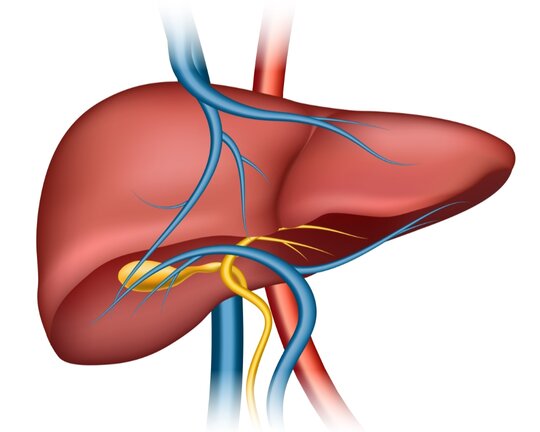

আমাদের শরীরের প্রতিটা অঙ্গই গুরুত্বপূর্ণ। ঠিক তেমনি লিভারও আমাদের শরীরের জন্য খুবই গুরুত্বপূর্ণ। লিভার বা যকৃত আমাদের শরীরে জমে থাকা টক্সিক বের করে দেয় । এই গুরুত্বপূর্ণ অঙ্গটি যদি তার কার্যকারিতা হারায় তাহলে আমাদের শরীরে টক্সিন তো থাকবেই সেই সাথে দেখা দেবে নানান রোগ ।

তো আজকে আমরা জানব কোন কারণে লিভার ক্ষতিগ্রস্ত হতে পারে ।